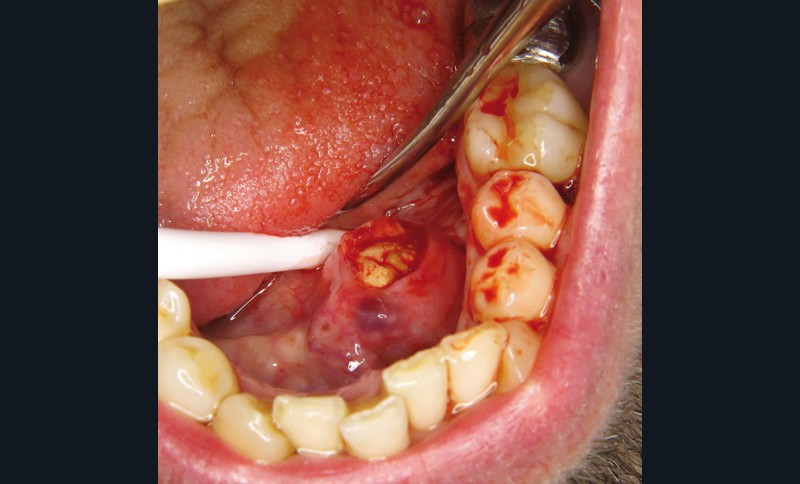

La prise en charge est chirurgicale sous anesthésie locale. Une incision du toit du nodule est réalisée (fig. 4 et 5).

La lithiase est libérée du canal aux ciseaux de Metzenbaum, ce qui permet son énucléation en un seul fragment de plus de 2 cm de grand axe (fig. 6).